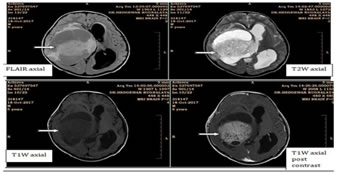

In our study, the cause of seizures in 4 patients was infection use tiology. Encephalitisin3patients (75%) and meningoencephalitisin1patient (25%). Thus, in our study, most common pathology in patients with infectious etiology was encephalitis followed by meningoencephalitis. In our study, 3 patients were found to have encephalitis. Out of them, 2 patients (66.7%) had basal ganglia/thalamic lesions. 2 patients (66.7%) demonstrated temporal lobe lesions. Frontal and parietal lobe lesions and cerebellarandbrainstemlesionswereseenin1patient (33.3%) each. Most common neuroimaging finding in patients with encephalitis was basal ganglia/thalamic lesions and temporal lobe lesions. Neoplasm comprised 2 patients in our study. DNET and Pilocytic astrocytoma were seen in 1 patient (50%) each.

4

Image 4: Large solid cystic lesion and solid part showing post contrast enhancement. A case of pilocyticastrocytoma.